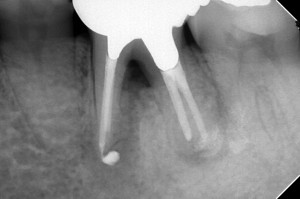

DB148536_160331163903(調整後)分岐部透過像、充填剤の押し出しが認められる

Project_20161209_000シーラー出すぎ( ;∀;)どやったらこんなんなるのよ|д゚)

DB148536_161209141752(調整後)術後半年。骨は出来ているが・・・